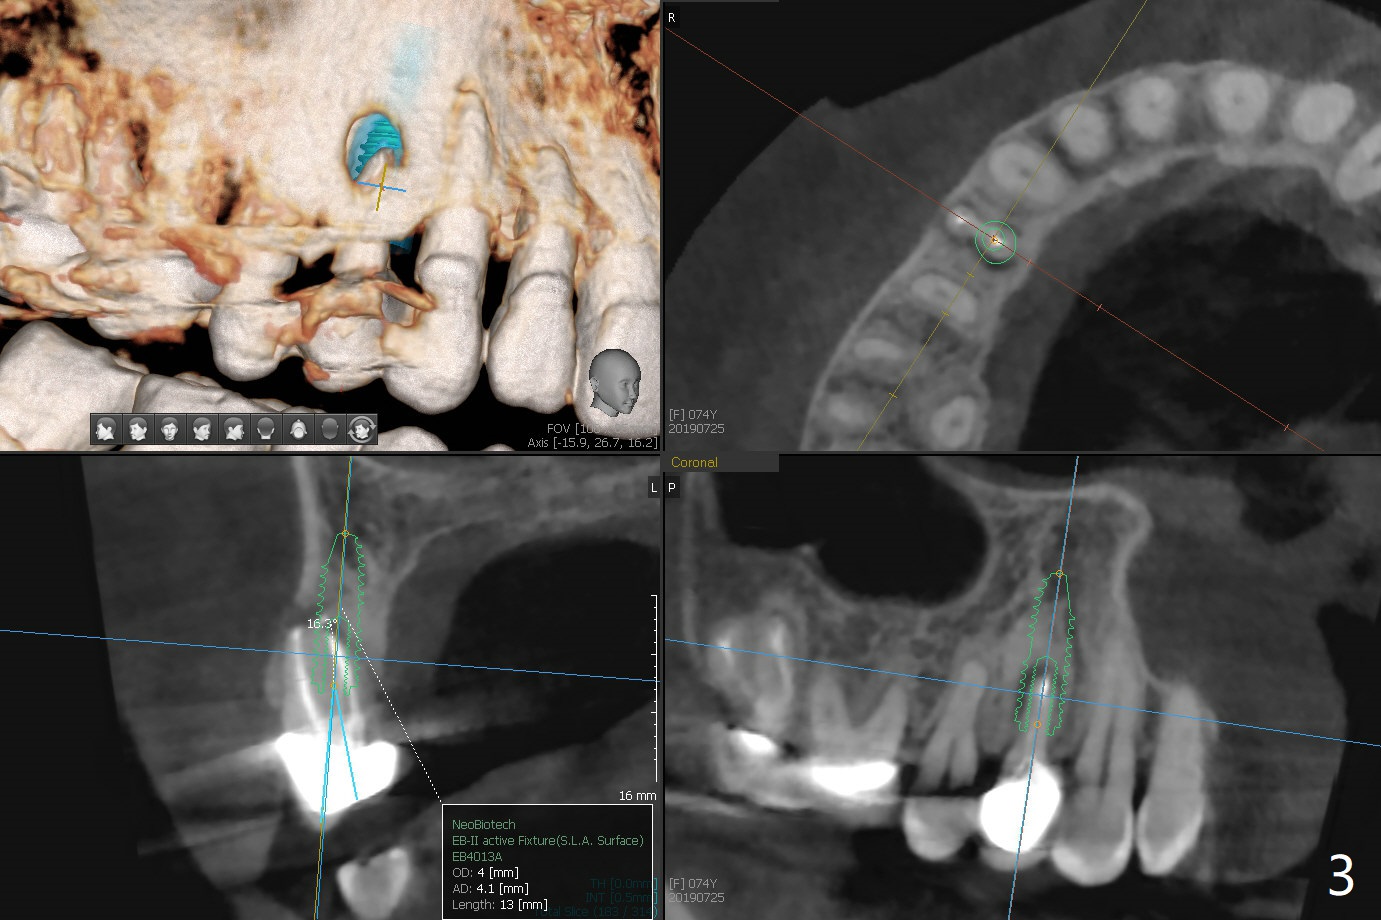

A 74-year-old woman is concerned about buccal fistula of the tooth #5 (Fig.1,2 >). It seems to be safe to place an immediate implant without too much possibility of developing periimplantitis in the future (Fig.3). With guide, restoration could be finished with a 15 degree angled abutment. Remove granulation tissue from the buccal fistula and from the socket. Place a piece of PRF membrane externally (tunnel incision, Fig.4-6 red line) or internally (from the socket) before bone graft (before and after implant placement (Fig.5,6 yellow circles)). Take 5x5 cm CT immediately postop to confirm the repair.